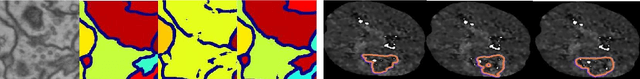

Abstract:The last decade of computer vision has been dominated by Deep Learning architectures, thanks to their unparalleled success. Their performance, however, often comes at the cost of explainability owing to their highly non-linear nature. Consequently, a parallel field of eXplainable Artificial Intelligence (XAI) has developed with the aim of generating insights regarding the decision making process of deep learning models. An important problem in XAI is that of the generation of saliency maps. These are regions in an input image which contributed most towards the model's final decision. Most work in this regard, however, has been focused on image classification, and image segmentation - despite being a ubiquitous task - has not received the same attention. In the present work, we propose MiSuRe (Minimally Sufficient Region) as an algorithm to generate saliency maps for image segmentation. The goal of the saliency maps generated by MiSuRe is to get rid of irrelevant regions, and only highlight those regions in the input image which are crucial to the image segmentation decision. We perform our analysis on 3 datasets: Triangle (artificially constructed), COCO-2017 (natural images), and the Synapse multi-organ (medical images). Additionally, we identify a potential usecase of these post-hoc saliency maps in order to perform post-hoc reliability of the segmentation model.

Abstract:Today, deep convolutional neural networks (CNNs) have demonstrated state-of-the-art performance for medical image segmentation, on various imaging modalities and tasks. Despite early success, segmentation networks may still generate anatomically aberrant segmentations, with holes or inaccuracies near the object boundaries. To enforce anatomical plausibility, recent research studies have focused on incorporating prior knowledge such as object shape or boundary, as constraints in the loss function. Prior integrated could be low-level referring to reformulated representations extracted from the ground-truth segmentations, or high-level representing external medical information such as the organ's shape or size. Over the past few years, prior-based losses exhibited a rising interest in the research field since they allow integration of expert knowledge while still being architecture-agnostic. However, given the diversity of prior-based losses on different medical imaging challenges and tasks, it has become hard to identify what loss works best for which dataset. In this paper, we establish a benchmark of recent prior-based losses for medical image segmentation. The main objective is to provide intuition onto which losses to choose given a particular task or dataset. To this end, four low-level and high-level prior-based losses are selected. The considered losses are validated on 8 different datasets from a variety of medical image segmentation challenges including the Decathlon, the ISLES and the WMH challenge. Results show that whereas low-level prior-based losses can guarantee an increase in performance over the Dice loss baseline regardless of the dataset characteristics, high-level prior-based losses can increase anatomical plausibility as per data characteristics.